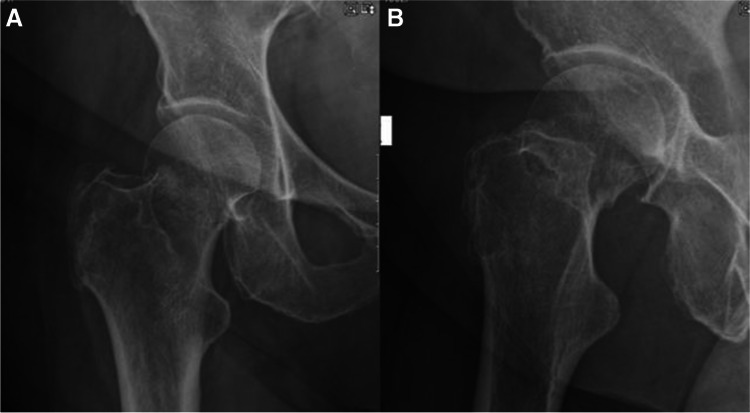

Fig. 1.

A, B AP and lateral radiographs showing intracapsular femur fracture of a 77-year-old female, which was admitted after a fall from standing height. Patient walks with no aids before the injury; her medical history consist of hypertension and dyslipidaemia